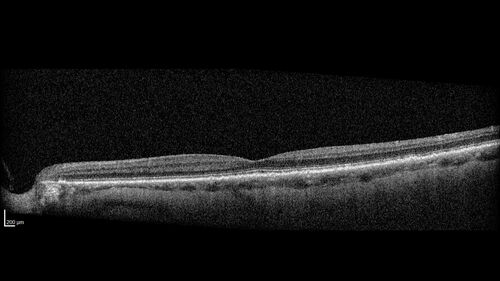

Hemi-CRVO - dual trunk vein

81 year old female mild vision loss - Anatomy shows dual trunk vein with one blocked. About 20 percent of people have this anatomy